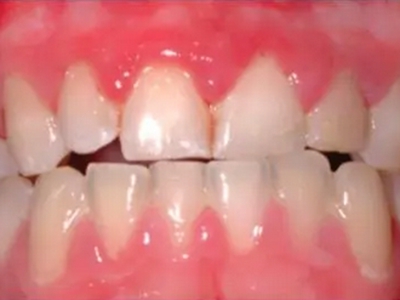

慢性龈炎又称边缘性龈炎或单纯性龈炎,主要表现为游离龈和龈乳头因炎性水肿,而变为鲜红或暗红色,龈缘变厚,龈乳头圆钝肥大。慢性龈炎的患病率高,治愈后仍可复发,部分患者可发展成为牙周炎。

慢性龈炎的病损部位一般局限于游离龈和龈乳头,以前牙区为主,尤其以下前牙区最为显著,患者常因刷牙或咬硬物时牙龈出血而就诊。游离龈和龈乳头颜色变为鲜红或暗红色,病变较重时炎性充血可波及附着龈。龈缘变厚,龈乳头圆钝肥大,可增生呈球状,覆盖牙面。牙龈松软脆弱,缺乏弹性。